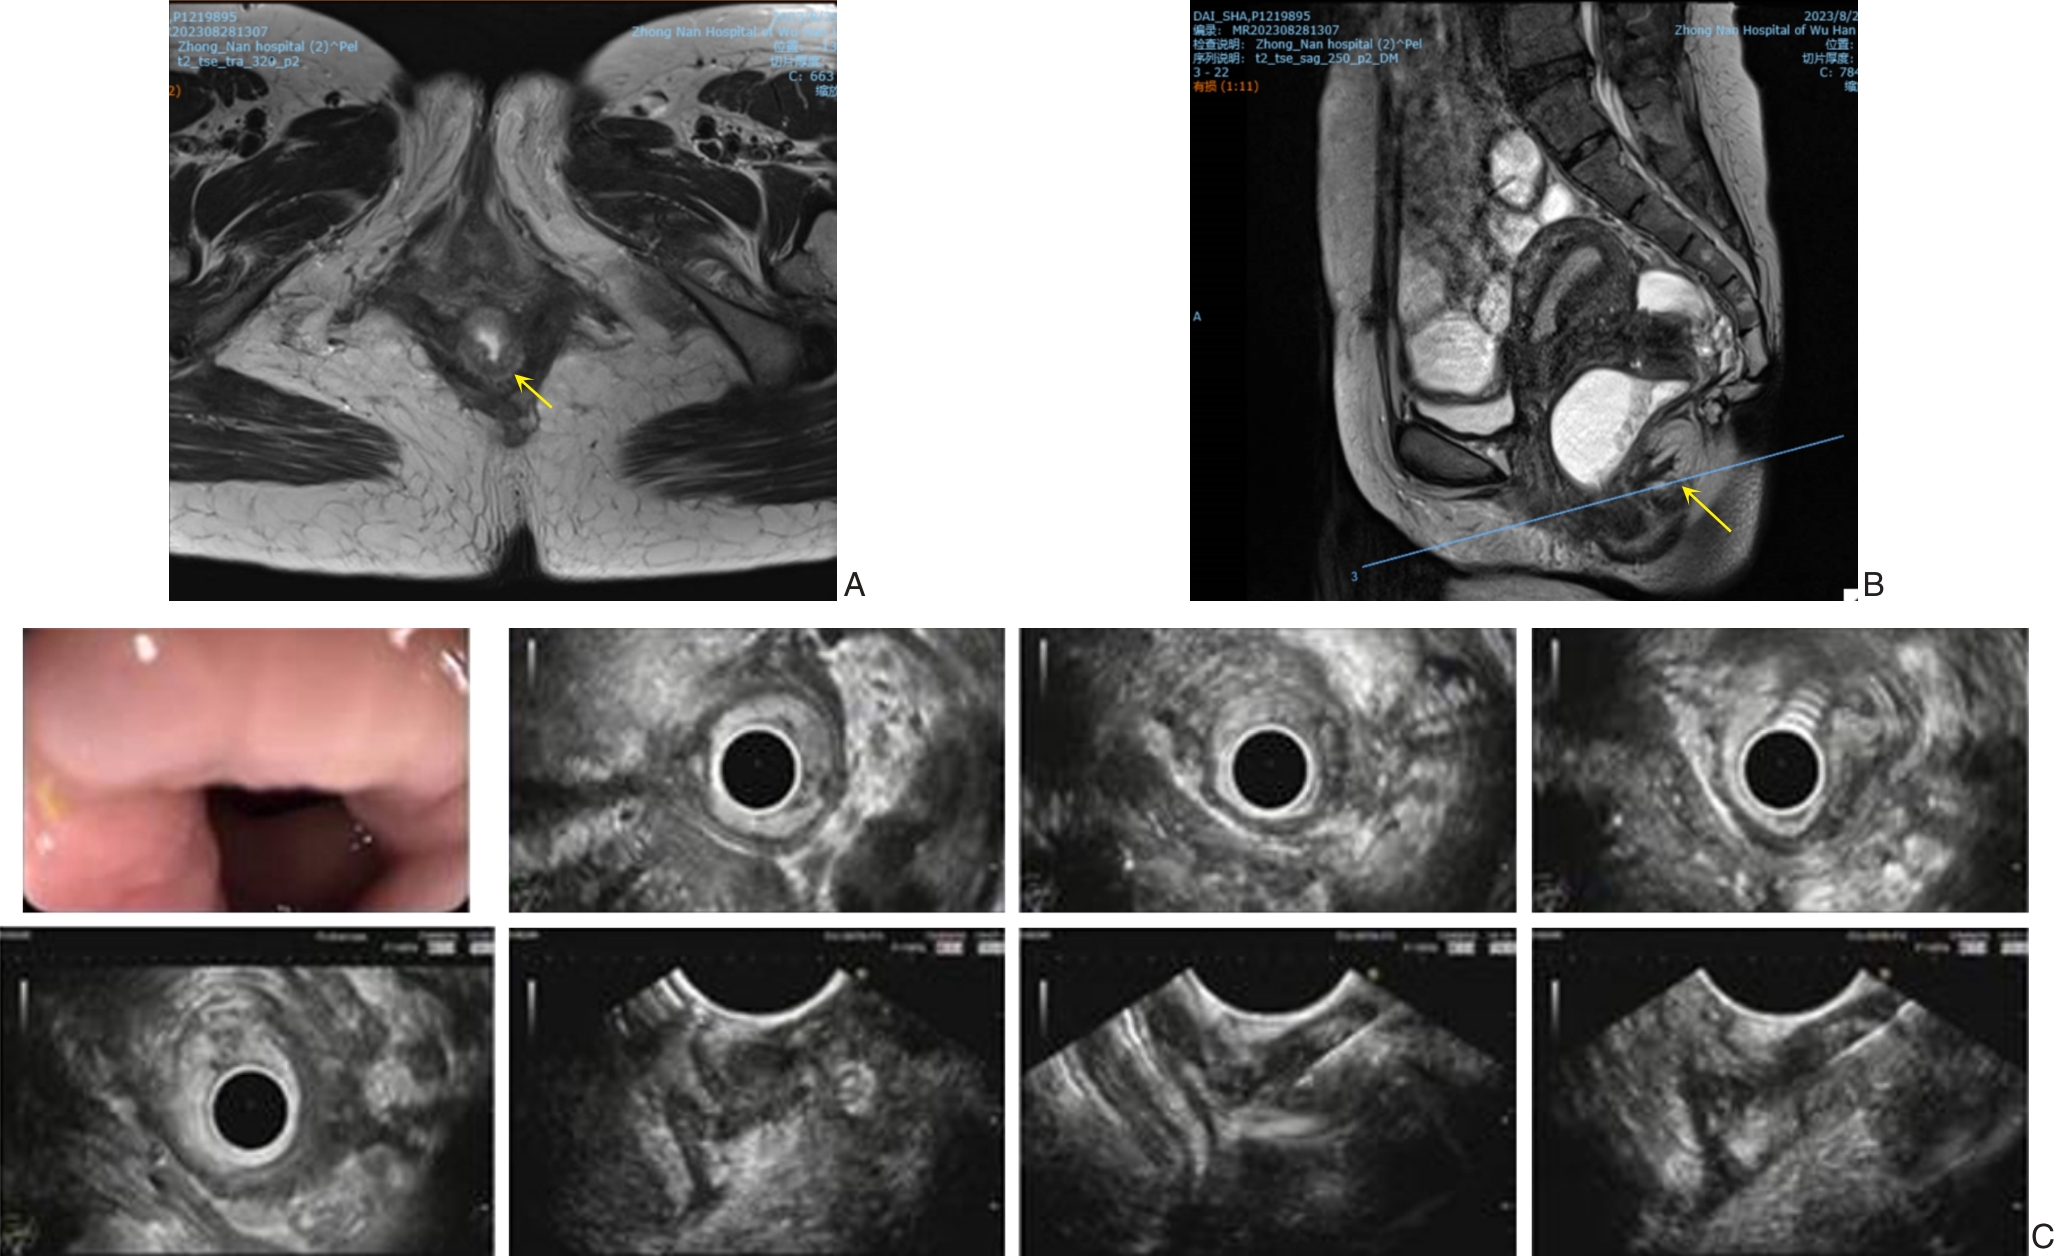

摘要:深部浸润型子宫内膜异位症(DIE)是指子宫内膜异位病灶浸润腹膜下≥5 mm,常累及宫骶韧带、阴道直肠隔、阴道穹隆及直肠壁等部位,因临床表现缺乏特异性、影像学特征不典型而易误诊。本研究报告1例术前经内镜超声引导下细针穿刺活检(EUS-FNA)确诊的直肠DIE患者,结合文献回顾,总结其多学科团队(MDT)诊治经验。患者为35岁女性,因排便困难入院,经MRI及EUS-FNA确诊为直肠DIE。经结直肠肛门外科、妇科及泌尿外科联合讨论后实施腹腔镜直肠病变切除、乙状结肠-直肠吻合及预防性回肠造口术,术后病理证实切缘阴性,4个月后成功还纳造口。随访21个月,患者症状明显缓解,未见复发。结果提示,EUS-FNA在DIE的早期诊断中具有重要价值,而以结直肠肛门外科为主导、妇科与泌尿外科协同的MDT模式可显著提高手术安全性和根治性,对复杂盆腔内异症的精准诊治具有重要指导意义。